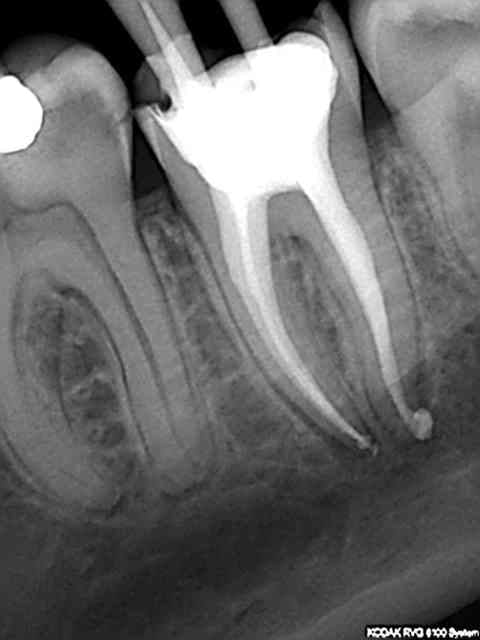

T'inquiètes il y en a qui ne sont pas stressés. On essaye de remonter le niveau, rien de sorcier il suffit de disposer du matos adéquat, endo master + S1 protaper et wd gold + R25 réciproc pour moi, Résultats reproductibles à 100%. La dernière de ce soir avant et après, un jeu.

Mais on est pas à l'abri d'un peuf à l'apex comme tout de suite. Arghhh, je ne vais pas en dormir !)))))))

Pas de digue sur ce coup ci, car paroi vestibulaire inexistante et 30 mn pour faire l'endo (dont 15 à l'endo activator et ca c'est long !)